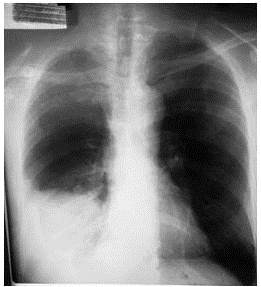

Paciente masculino de 63 años de edad con antecedente de diabetes mellitus tipo II, enfermedad tabáquica una cajetilla de cigarros diaria por 20 años, quien inicia enfermedad actual hace tres meses cuando comienza a presentar dolor en la parte inferior de la pared de hemitórax derecho, de tipo punzante de moderada intensidad, sin irradiación acompañándose de disnea progresiva por lo cual consulta es valorado, a la exploración física del tórax; refiere dolor a la palpación, a la percusión matidez a nivel de la base derecha e igualmente disminución de los ruidos respiratorios a la auscultación. Por lo cual se decide pedirle una radiografía de tórax póstero-anterior en donde se evidenció una imagen de opacidad en el campo pulmonar derecho a nivel de su base, densa homogénea sin broncograma aéreo que borra la visualización del contorno cardíaco, asimismo, los ángulos costofrénicos y cardiofrénicos con compatibilidad para el diagnóstico de derrame pleural maligno por lo antecedentes tabáquicos del paciente (Figura 5).